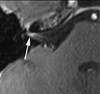

You see a patient with this MRI. What histologic findings would you expect if this was found to be a glial neoplasm?

This MRI is suggestive of a pilocytic astrocytoma, given the cystic component with an enhancing nodule. Histologically, these tumors demonstrate parallel arrangement of bipolar astrocytes with Rosenthal fibers and eosinophilic granular bodies.